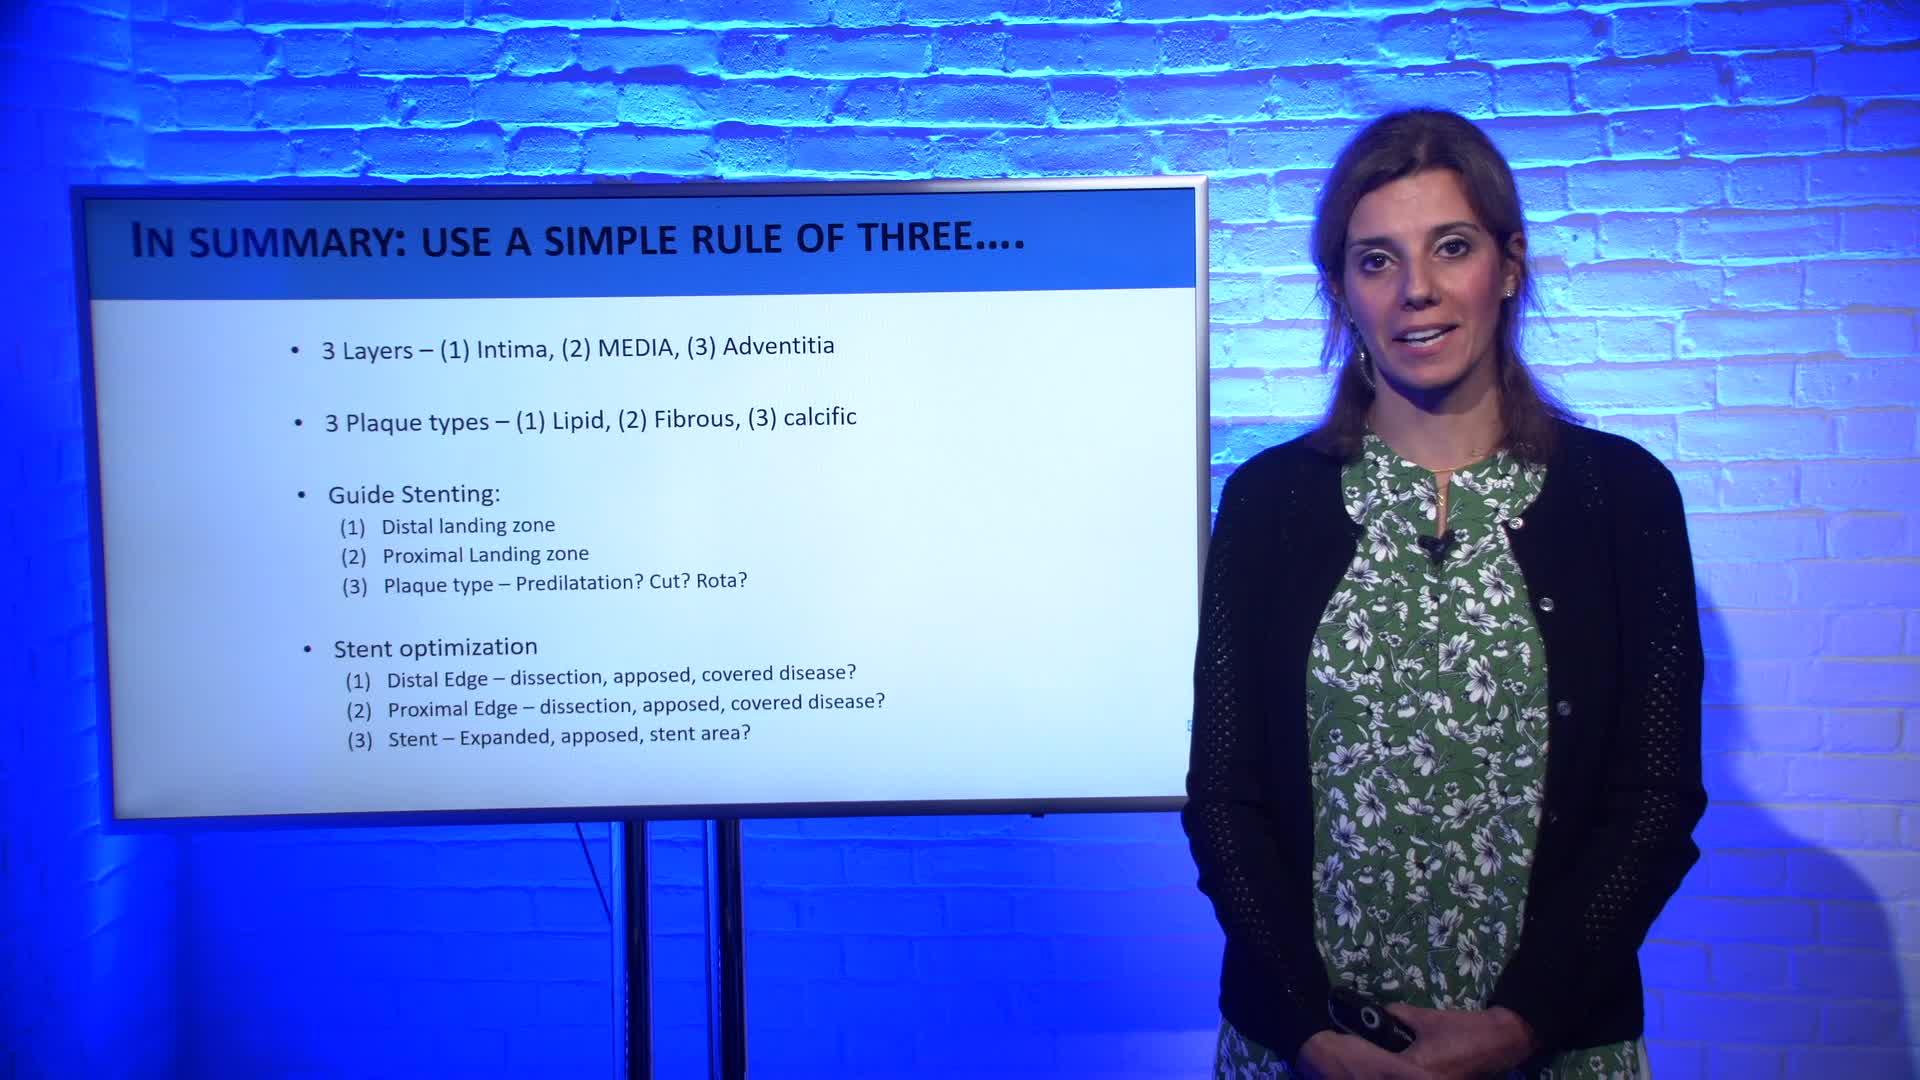

How to perform good co-registration measurements using iFR and IVUS - Prof Carlo Di Mario

Essential steps for physiology-based PCI planning and guidance - Dr Allen Jeremias

Essential Guide to Intra-coronary Imaging for the General Cardiologist - Dr. Iqbal Malik